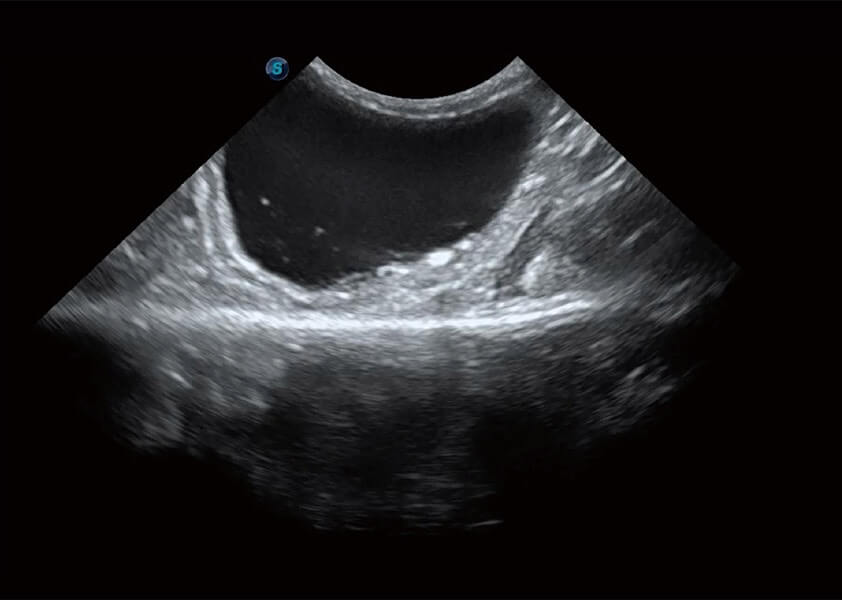

ProPet 60 作為一款高端臺式動物超聲設(shè)備,為動物醫(yī)生的日常診斷提供了一系列貼合動物臨床需求、解決臨床實際問題的高級成像功能。憑借全系列高清探頭,滿足醫(yī)生對腹部、心臟、生殖、淺表、肌骨等成像的所有需求,切實幫助您提升檢查效率,提高診斷信心。